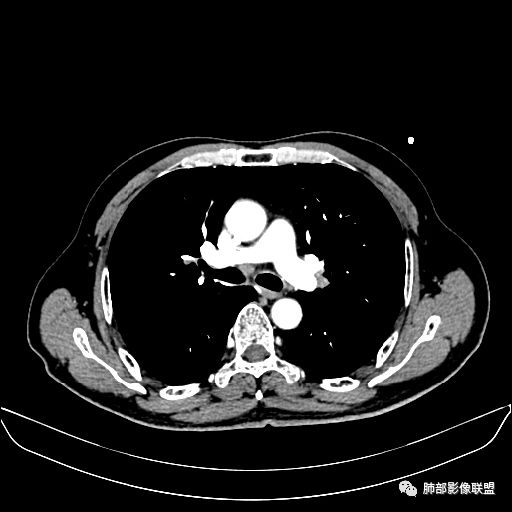

住院4天后行胸部增强CT

静脉期

老年男性,因“咳嗽咳痰1月余。”入院。病程中咳嗽咳痰,咳黄白痰,间断咯少许鲜红色痰血。PPD阳性。胸CT:右肺中叶外侧段支气管管腔阻塞,大片实性病变,病灶边缘光滑,部分边缘膨隆,可见分叶,肺门及纵隔可见肿大淋巴结,并可见钙化。增强可见病灶明显强化,而且延迟强化明显,病灶内多发低密度区,内见血管影,血管变细、部分血管破坏。考虑恶性病变可能性大,鉴别慢性肉芽肿性病变。

胸CT:跨叶大肿块,主体在中叶,右中叶外侧段支气管阻塞,病灶部分边缘膨隆,可见分叶,部分边缘平直,肺门及纵隔可见肿大淋巴结。增强病灶不均匀强化,延迟强化明显,病灶内多发低密度区,内见血管飘浮,部分血管变细、模糊。考虑:恶性病变可能性大,大细胞?淋巴瘤?鉴别慢性肉芽肿性病变。

右肺中叶软组织肿块,外围向内生长,叶间胸膜向前内移位,肿块近肺门侧跨叶,中叶外侧段支气管截断,密度不均匀,双侧肺门及隆突下见肿大淋巴结,增强后呈中度不均质强化,肺动脉供血,多发坏死区,边界尚清,坏死区域内见结构,结合病史考虑恶性,鉴别诊断1结核,爬行征是沿支气管树分布,外宽,内窄,周围有卫星灶,内气管狭窄后扩张,此例沿叶间胸膜长轴分布,气管有截断,不典型。2炎性肉芽肿,符合的地方下方层面增强后延迟性轻度环形强化,不符临床无发热等急性感染病史,实验室指标不符,病灶周围渗出及慢性炎性改变有,不明显。